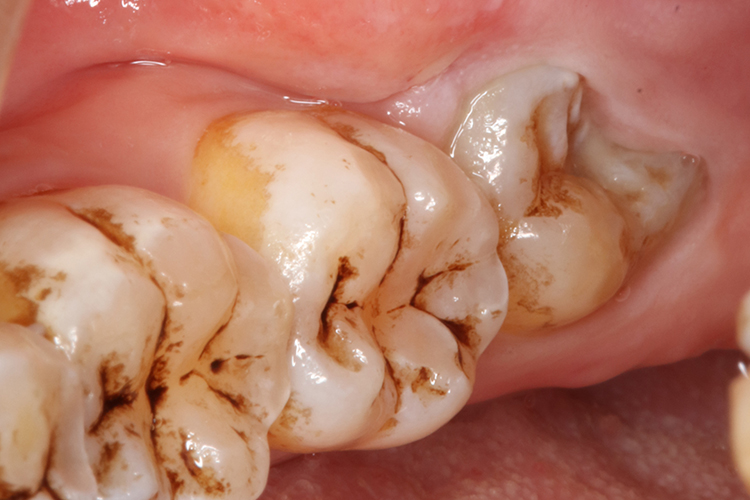

是指第三恒磨牙由于受颌骨和其他牙齿的阻碍,无法完全萌出,导致部分牙体被牙龈覆盖,以下颌第三颗磨牙最为常见。阻生智齿可能向各个方向倾斜萌出,但多见向前方倾斜萌出。阻生智齿的牙体和牙龈之间存在较深的间隙,易积留食物残渣,导致细菌滋生、繁殖而引起智齿冠周炎。

牙齿周围红肿疼痛,有时龈袋内有脓性分泌物溢出,造成张口困难,颌下淋巴结肿大压痛,这时如不及时治疗,炎症将继续发展,引起面部明显肿胀、全身不适、发烧、食欲减退、大便秘结等症状。